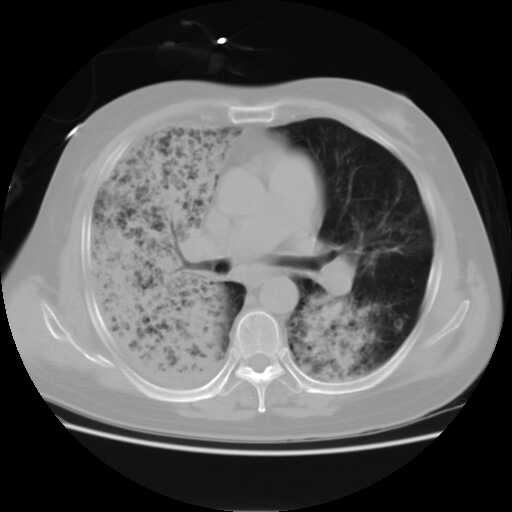

2008.8.17ct定位片

2008.8.17ct

病变从8.11-8.17明显改变,增多,以蜂窝状改变为主,类蜂窝肺,似弥漫性肺泡癌,但是病变进展太快,不符合弥漫性细支气管肺泡癌。因此考虑为特殊微生物感染,多以霉菌类常见,建议细菌微生物学检查。

疑点二:影象表现怪异,大片阴影内见多发筛孔征,如何解释.